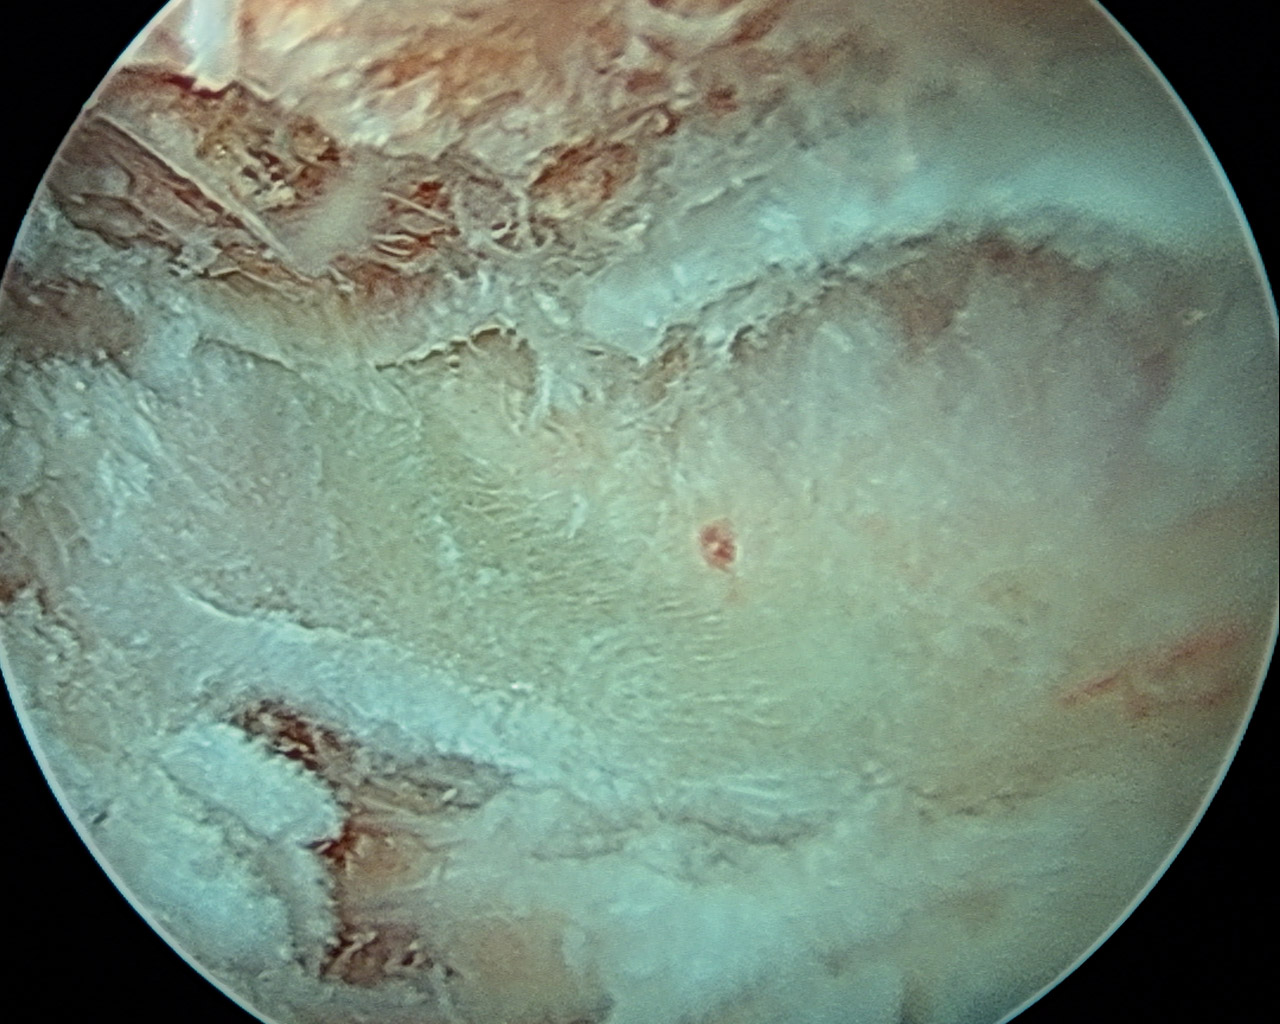

A través del portal de trabajo y con ayuda de sinoviotomo y radiofrecuencia, se procedió a la extirpación del tejido fibroso y bursal para exponer el ángulo superomedial de la escápula, localizado mediante palpación directa y la movilización indirecta de la escápula al mover el brazo (Figura 4).

Figura 4. A: visión inicial del espacio escapulotorácico; B: limpieza de tejido fibroso, bursal y cicatricial con ayuda de sinoviotomo hasta localización del borde superomedial escapular; C: exposición de dicho borde y preparación para realización de osteotomía; D: con ayuda de una fresa de 4 o 4,5 mm, se procede a la resección del borde superomedial escapular.

En todos los casos se realizó extirpación parcial del ángulo superomedial de la escápula mediante fresa de 4 mm de diámetro, con unas dimensiones aproximadas de 2 cm en el plano anteroposterior y 2 cm en el plano mediolateral (Figura 5). Para el cierre de los portales se utilizó un monofilamento.